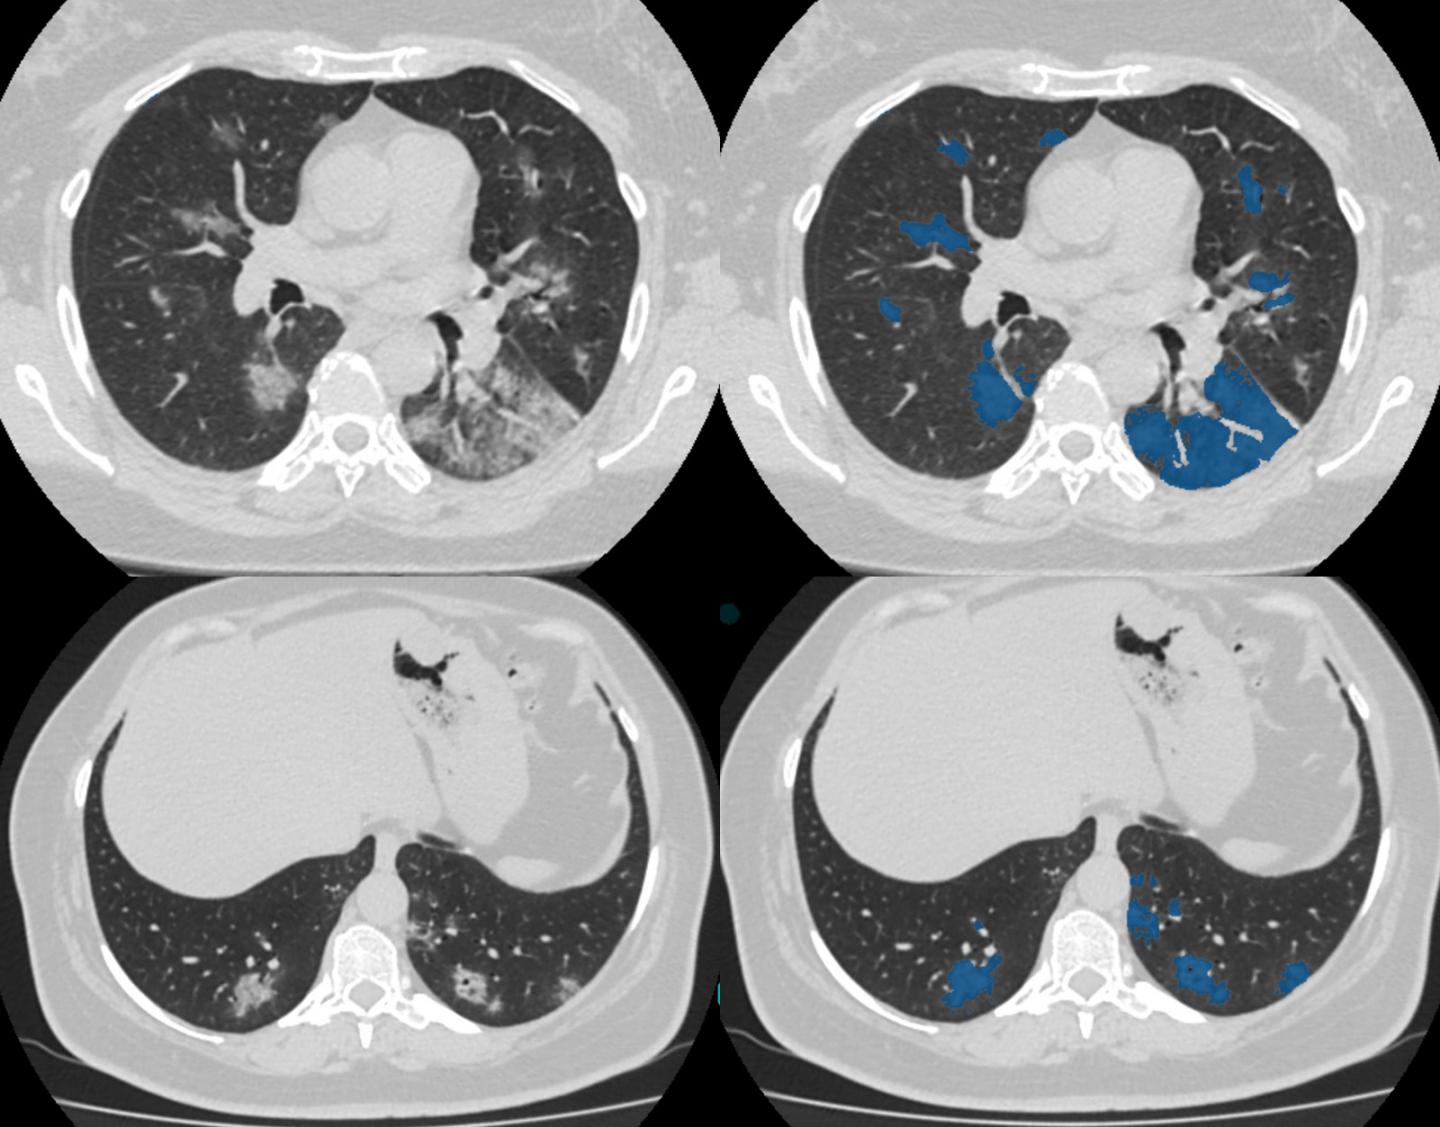

Ct Scan 7 Months After Completion Of Adjuvant Chemotherapy Chest Ct Download Scientific Diagram